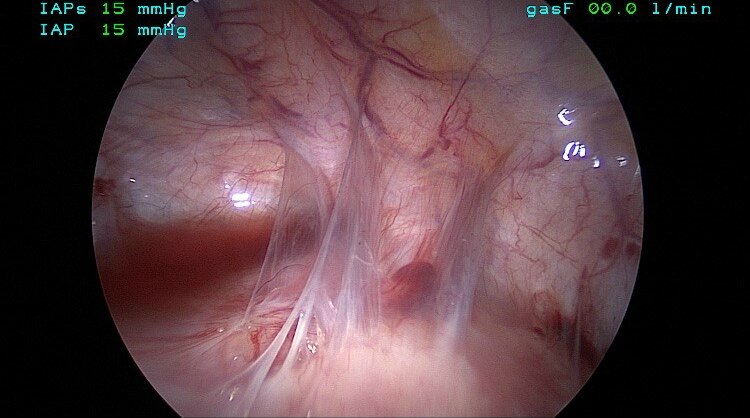

Laparoscopic Surgery Adenomyosis With Bilateral Ovarian Endometriosis By Yuna Hawal

Laparoscopic Surgery Adenomyosis With Bilateral Ovarian Endometriosis By Yuna Hawal from i.ytimg.com